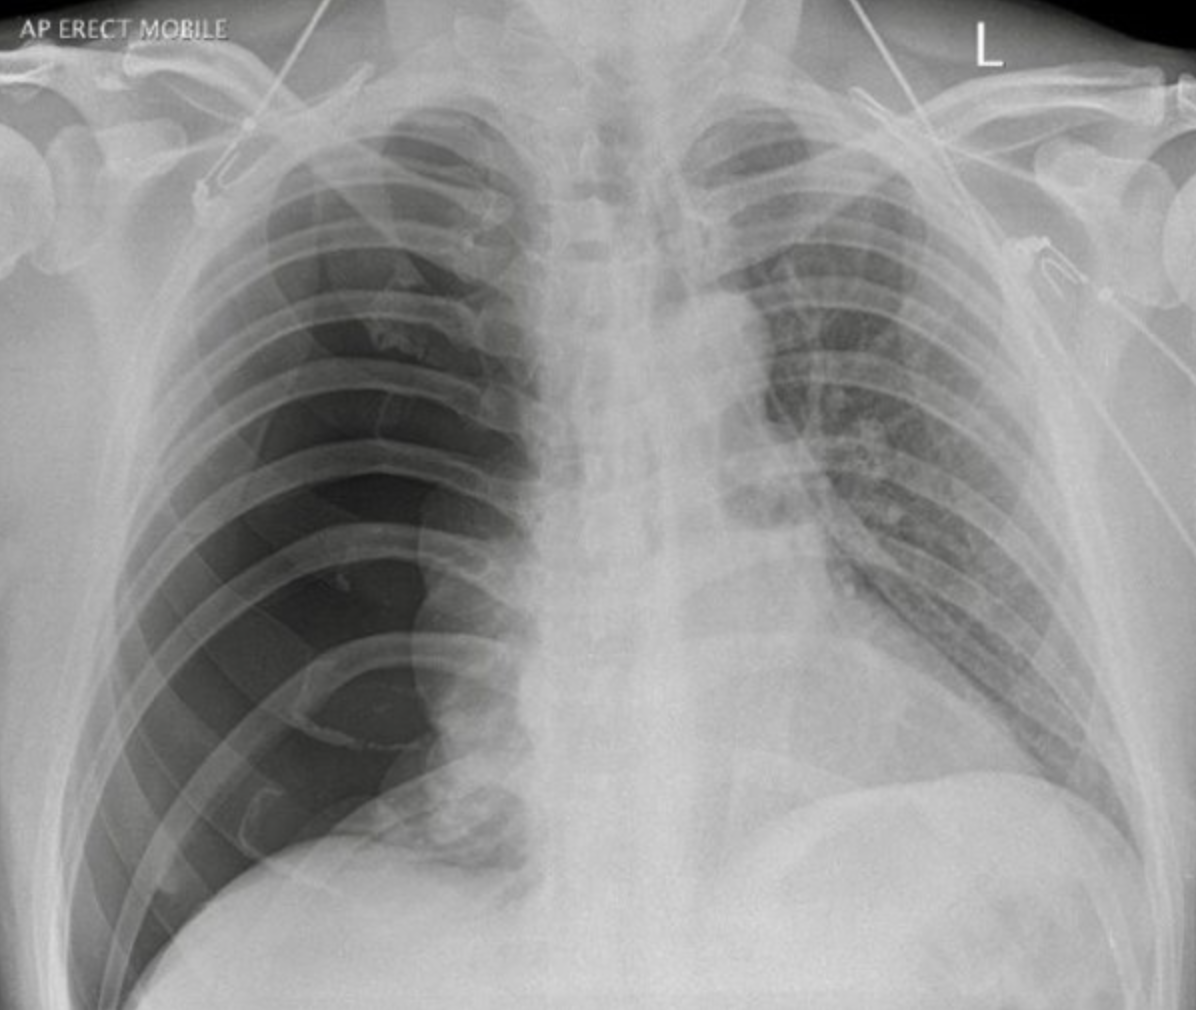

What is this?

(name the acute condition)

Patient has COPD

A

Right sided secondary spontaneous pneumothorax.

(secondary because the patient has an underlying lung condition)